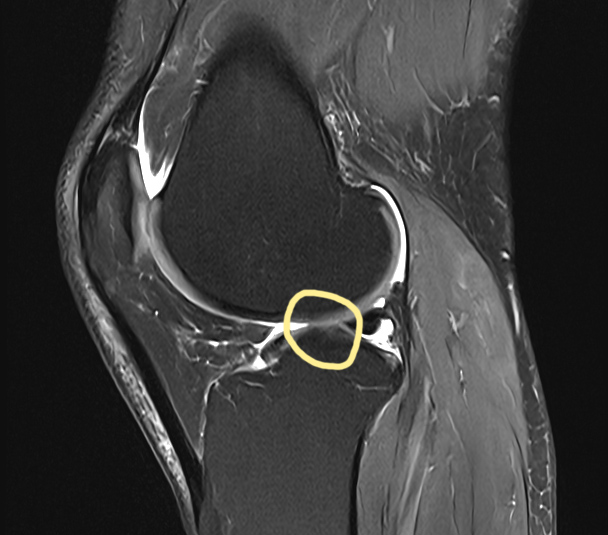

Erstes MRT Ende August 2023

Erst so spät erhalte ich einen MRT-Termin, im Sommer geht alles langsamer wenn es nicht akut ist. Der Operateur fragt mich danach ob ich bald einen Termin beim Orthopäden habe. Ich verstehe die Frage nicht so recht, ich kann ja noch einigermassen gut gehen wenn ich meine tägliche Gehdauer beschränke. Er scheint schon gesehen zu haben, dass etwas nicht stimmt. Ich bekomme zwar das Bildmaterial ausgehändigt, das kann ich aber nicht deuten. Der Befund wird erst am folgenden Tag ausgestellt und geht an den Hausarzt. Ich will aber nicht extra hingehen und lasse den MRT-Befund nur vom Hausarzt zum Orthopäden faxen. Laut Versicherung dürfen die Ärtze solche Daten nur faxen, so wie in den 1980er Jahren. Meine ausdrückliche Bitte mir den Befund per Email zu schicken wurde verwehrt. Vielleicht hat mich das auch davor bewahrt mir zu früh Sorgen zu machen, denn der Befund spricht Klartext.

Untersuchungsdatum: Innsbruck, am 24.08.2023

Knie rechts MRT Standardsequenzen nativ.

Befund: Flaues Knochenmarködem subchondral anterior und posterior am Tibiaplateau. Kleine viertgradige Knorpeldefekte retropatellar. Sonst unauffälliges Knochensignal. Femorotibial ausgedünnte Knorpelüberzüge bis Chondromalazie Grad II.

Komplexer, vorwiegend schräg verlaufender Einriss am Hinterhorn des Meniscus medialis. Geringe zentrale Meniskopathie im Hinterhorn des Meniscus lateralis. Intraartikulär keine verlagerten Meniskusanteile.

Regelrechte Durchgängigkeit des Ligamentum cruciatum anterius und Ligamentum cruciatum posterius. Unauffällige Darstellung des Ligamentum collateraie mediale und Ligamentum kollaterale laterale. Unauffälliger Tractus iliotibialis.

Unten eine Seitenansicht aus dem MRT. Im Gegensatz zum MRT von Ende August 2023 ganz oben auf der Seite, stehen die Knochen näher beisammen, das heisst, dass der Innenmeniskus an dieser Stelle in diesen 2,5 Jahren stark ausgedünnt wurde.